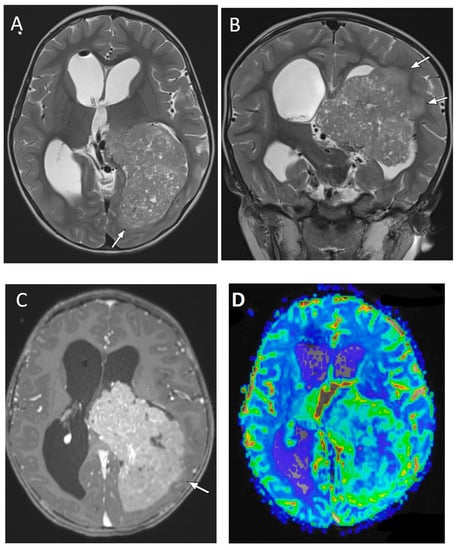

| Posterior fossa ependymoma | Fourth ventricle (PFB) or cerebellopontine angle (PFA) | Heterogeneous mass Calcifications common Intermediate diffusion (between medulloblastoma and pilocytic astrocytoma) Usually enhancing High myo-inositol on MRS |

| Medulloblastoma | Exclusively posterior fossa Most commonly in fourth ventricle/cerebellar vermis (non-WNT, non-SHH, or WNT), can involve cerebellopontine angle (WNT) or cerebellar hemispheres with extra-axial extension (SHH) | Diffusion restricting Variable enhancement Cystic/necrotic change may be present Calcifications uncommon Taurine peak characteristic |

| Atypical teratoid/rhabdoid tumor | Posterior fossa (slightly more common) or cerebral hemispheres May be extra-axial | Diffusion restricting Enhancement usually present More heterogenous than medulloblastomas, with cysts/necrosis, calcification, and hemorrhage |